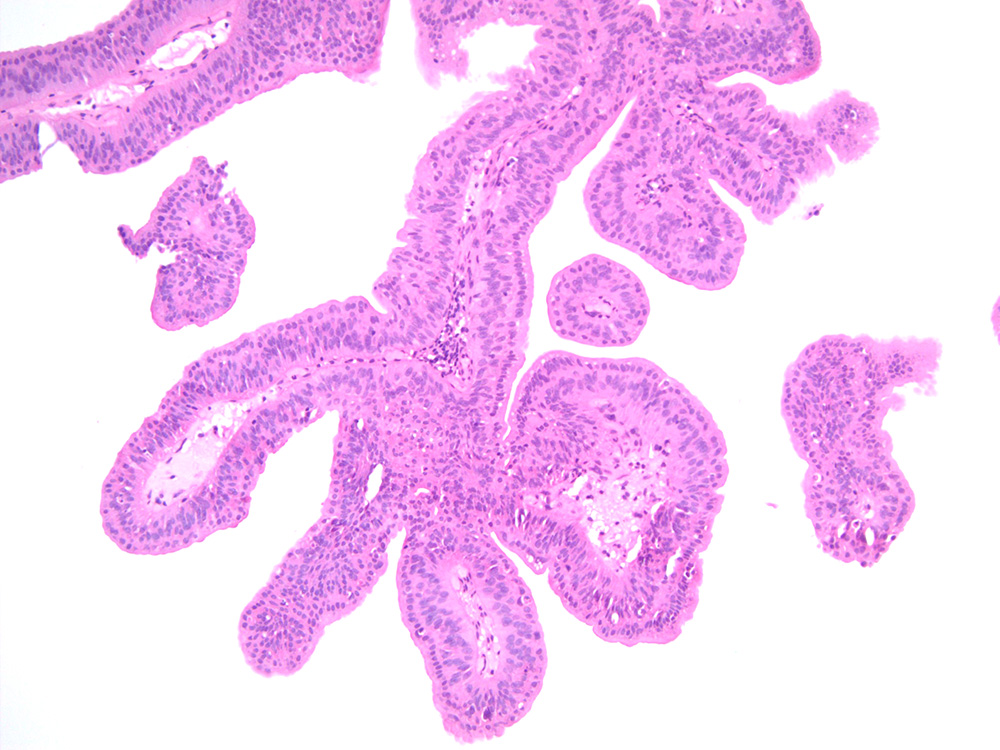

Consensus grade: Papilloma

Small papillary lesion in urinary bladder